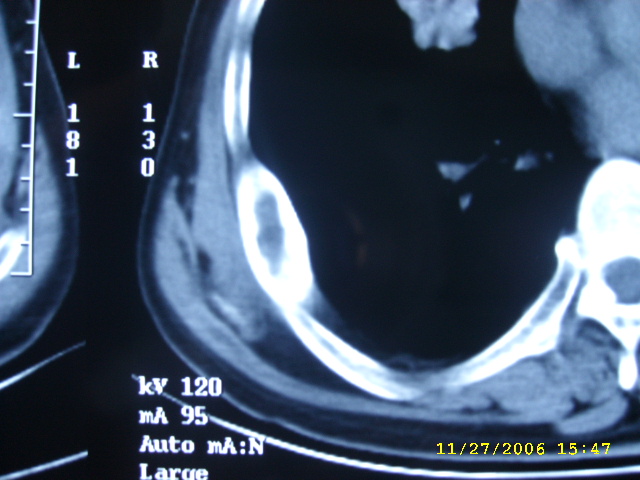

如果右肺病变与肋骨病变联系起来考虑:1右肺周围ca并肋骨转移;2:嗜酸性肉牙肿?

肺部病变先考虑周围性肺癌,肋骨病变不象破坏和转移,应考虑骨纤.一影论影.

1右肺周围ca

右侧周围型肺癌伴肋骨转移.

右侧肺癌,右侧肋骨转移?

周围型肺癌.肋骨可能是陈旧骨折愈合.

右肺内病变考虑肺癌,右侧肋骨局部增粗,皮质增厚,髓腔增宽,有否陈旧骨折?先考虑骨纤维异常增殖症。

1.右下肺病灶周围型肺癌的可能性非常大。

1.右侧周围型肺癌.

肺部病变考虑周围性肺癌,肋骨病变考虑骨纤